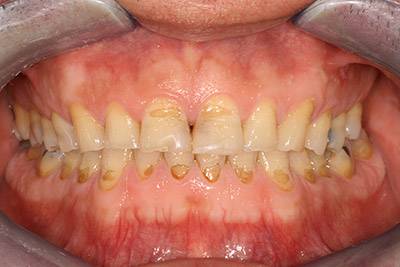

Nagymértékű fogkopás, erózió, csikorgatás a teljes rágóapparátust túlterhelve okoz reménytelennek tűnő helyzeteket.

Ebben az esetben implantátumok , koronák és hidak segítségével változtattunk a páciens fogainak érintkezésén. 6 hónapig ideiglenes hidakkal teszteltük a megváltoztatott harapási pozíciót. Ezután készültek el a végleges fix pótlások.